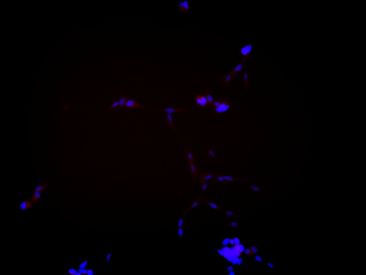

神経芽腫細胞の増殖の様子を対数軸目盛りで表現したもの

神経特異的マーカー(赤)、 核(青)

小児外科学教室を志望したのは、数ある「生命医科学研究入門」での研究内容紹介の中でもっとも私の知的好奇心を刺激したからです。そのときの発表テーマは、小児がんの神経芽腫でした。神経芽腫は、ある日突然スイッチが切れたかのように一斉に身体中から消失してしまうことがあるという不思議な腫瘍です。この性質そのものに興味を抱いただけでなく、どのような方法でこれを解明していくかも気になったため、感想文にアツく志望理由をしたため、無事に受け入れていただくことになりました。

私はまず神経芽腫に関する基本的な知識を学習しました。そしてそのあと桐野助教と大学院生の下で、『交感神経の分化に関連する遺伝子の発現を制御して神経芽腫の退縮を誘導するような新規分化誘導因子の開発に向けた一研究』が行われる様を体験しました。具体的には神経芽腫細胞の培養と神経特異抗原の免疫染色を行いました。このような具体的な実験手法を学ぶことももちろん重要なことであったのですが、最も重要な学びは別にありました。